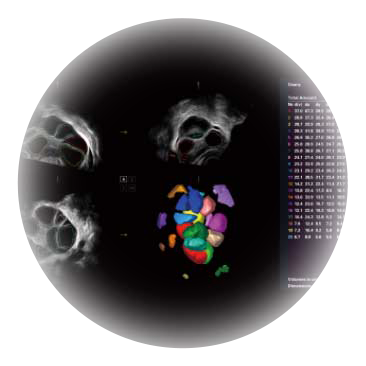

• AVC Follice卵泡自动测量

卵泡结构的自动识别和测量,可显示多组测量数据。

• 专业盆底应用

大角度腔内容积探头,可完整包络子宫及盆底结构,充分展示组织结构毗邻关系。